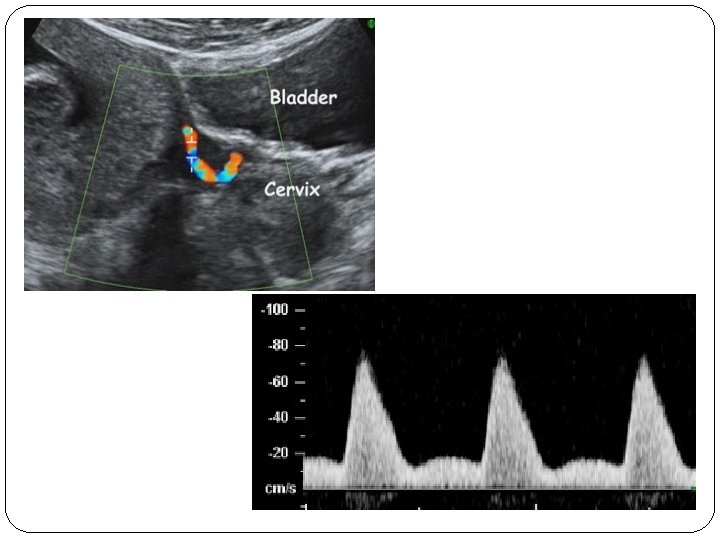

�measurement of the uterine artery pulsatility index (PI) at 11 -13 weeks' gestation in combination with maternal history(inc) mean arterial pressure(inc) serum PAPP-A(dec…>inc) placental growth factor (PLGF) (dec…>inc) �The factors in the maternal history that appear to make a significant independent contribution to the preeclampsia risk assessment included maternal BMI, age, ethnicity, smoking, and parity.

� early rather than late preeclampsia is associated with an increased risk of perinatal mortality and morbidity and both short-term and long-term maternal complications. � Combination of the above mentioned risk factors was shown to predict 90% of early preeclampsia, 35% of late preeclampsia, and 20% of gestational hypertension. � This compares favorably with screening based on maternal history alone where only 30% of early and 20% of late preeclampsia are predicted for a 5% false positive rate.

�Sagittal section of the uterus must be obtained and the cervical canal and internal cervical os identified. Subsequently, the transducer must be gently tilted from side to side and then colour flow mapping should be used to identify each uterine artery along the side of the cervix and uterus at the level of the internal os. �Pulsed wave Doppler should be used with the sampling gate set at 2 mm to cover the whole vessel and ensuring that the angle of insonation is less than 30º. When three similar consecutive waveforms are obtained the PI must be measured and the mean PI of the left and right arteries be calculated

confirm that the vessel being � 1 -the direction of the blood flow should be towards the transducer when the transabdominal approach is used. This assures that the cervical branches are not being insonated. � 2 -the peak velocity of the insonated vessel should be 60 cm/sec or greater. This assures that the main uterine artery is being insonated rather one of its branches.